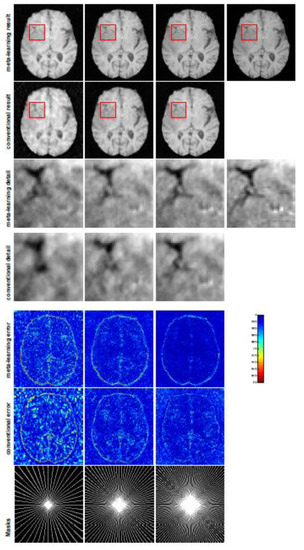

A qualitative comparison between conventional and meta-learning methods is shown in Figure 1 and Figure 2, displaying the reconstructed MR images of the same slice for T1 and T2, respectively. We label the zoomed-in details of HGG in the red boxes. We observe evidence that conventional learning is more blurry and loses sharp edges, especially with lower CS ratios. From the point-wise error map, we find that meta-learning has the ability to reduce noises, especially in some detailed and complicated regions, compared to conventional learning.

To verify the reconstruction performance of the proposed LOA 1, we compared the proposed conventional learning with ISTA-Net + [54], which is a state-of-the-art deep unfolded network for MRI reconstruction. We retrained ISTA-Net + with the same training dataset and testing dataset as conventional learning on the T1-weighted image. For a fair comparison, we used the same number of convolution kernels, the same dimension of kernels for each convolution during training, and the same phase numbers as conventional learning. The testing numerical results are listed in Table 1 and the MRI reconstructions are displayed in Figure 1. We can observe that the conventional learning which unrolls Algorithm 1 outperforms ISTA-Net + in any of the CS ratios. From the corresponding point-wise absolute error, the conventional learning attains a much lower error and much better reconstruction quality.